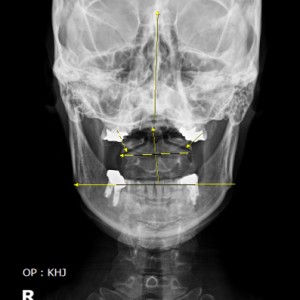

안면 두개골 엑스레이 검사

Submento Vertex View 포함

안면 균형검사

턱의 다양한 각도 사진 촬영

전신 엑스레이 검사

턱, 어깨 높이, 골반 틀어짐, 부정렬